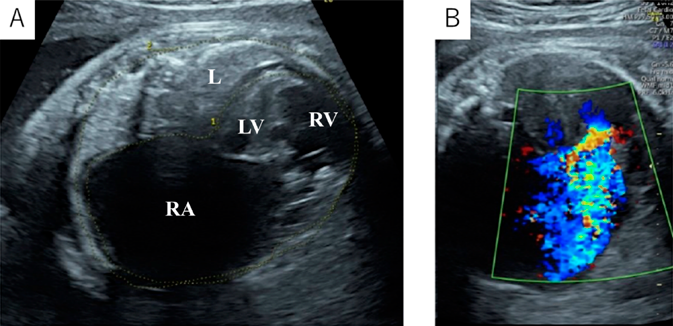

At 37 weeks 5 days’ gestation, a 2,756 g female baby was delivered via elective cesarean section. Artificial ventilation was begun, and prostaglandin was administered. Saturation of percutaneous oxygen (SpO2) increased from 20% to 50%. Apgar scores were 2 and 2 at 1 and 5 minutes after birth, respectively. A chest radiograph showed severe cardiomegaly and a cardiothoracic ratio of 98% (Fig. 2). An echocardiography confirmed the prenatal diagnosis and showed massive tricuspid regurgitation. She continued to be hypoxic with SpO2 at 50% after intubation. Within 92 minutes after birth, surgery was initiated using cardiopulmonary bypass with an arterial cannula into the ascending aorta and bi-caval venous cannulae. The ductus arteriosus was ligated, and the tricuspid valve annulus was closed using a 0.4 mm expanded polytetrafluoroethylene patch with a 3 mm-diameter hole. The atrial septum and the dilated right atrial wall were excised widely. After aortic unclamping, the right ventricular wall was plicated longitudinally using 3-0 braids (Nespolene®, Alfresa, Osaka, Japan). An aorto-pulmonary shunt was constructed, using a 3.0 mm-diameter expanded polytetrafluoroethylene tube graft, between the brachiocephalic artery and the right pulmonary artery. During weaning from cardiopulmonary bypass, hypoxia and hypoventilation were observed. Therefore, HFV (fraction of inspired oxygen (FiO2), 100%) with inhaled nitric oxide (iNO) 20 ppm was used to successfully wean from cardiopulmonary bypass. The patient was returned to the intensive care unit with her chest open.

Fig. 2 Chest radiographs. (A) Immediately after birth. (B) After right ventricular exclusion procedure. (C) After introduction of VV ECMO. A white arrow shows 13 Fr blood access catheter. (D) After chest closure.

On the postoperative day 3, severe hypoxia suddenly developed (SpO2 decreased from 82% to less than 50%), followed by hypotension. An echocardiogram detected smooth flow across the aortopulmonary shunt and good left ventricular function. Therefore, we determined that the cause of hypoxia was due to pulmonary insufficiency, not because of an issue related to pulmonary blood flow. We decided to utilize VV ECMO. A 13 Fr double-lumen blood access catheter (Power Trialysis®, Becton Dickinson Inc., NJ, USA) was inserted from the right atrial appendage to the inferior cava vein. Venous blood was withdrawn from the tip of the catheter, and oxygenated blood was sent back into the atrium (Fig. 3A). VV ECMO (50 mL/kg/min, FiO2 100%) was initiated. Hemodynamics improved dramatically and stabilized. We performed systemic heparinization to maintain an Activated Clotting Time of 200 to 250 seconds during VV ECMO. HFV, minimal catecholamine support (dopamine: 2 µg/kg/min), and surfactant therapy were administered. We performed lung recruitment every day and reduced iNO from 20 to 1 ppm. After 7 days on ECMO, the lung fields on the chest radiograph improved and the ECMO flow was gradually decreased to the flow of 20 mL/kg/min with FiO2 30%. On postoperative day 12, VV ECMO was separated (Fig. 3B). The patient was weaned from iNO on the postoperative day 13 and had her chest closed on the postoperative day 24 with no problems in cardiac and lung function. She was discharged on postoperative day 106 (SpO2 90% in room air). The non-fenestrated Fontan circulation was established two years and nine months following the bidirectional Glenn procedure. Preoperative catheterization before the Fontan procedure showed pulmonary artery index of 215 mm2/m2 and pulmonary vascular resistance of 1.6 U·m2. The six-year-old has normal activity without a neurological deficit.